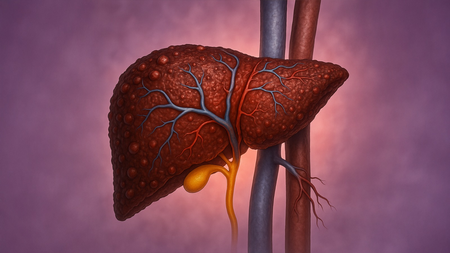

नई दिल्ली, 3 नवंबर (आईएएनएस)। फैटी लिवर आम लेकिन एक गंभीर समस्या है। शुरुआत में यह दर्द नहीं देता, इसलिए लोग इसे अनदेखा कर देते हैं, लेकिन धीरे-धीरे यकृत की अग्नि और क्षमता कमजोर होने लगती है। थकान, पेट में भारीपन, अपच, मितली और मन बोझिल महसूस होना इसके शुरुआती संकेत हैं।

आयुर्वेद में यकृत पित्त का मुख्य स्थान है। जब पित्त असंतुलित हो जाता है, कफ बढ़ जाता है और अग्नि मंद पड़ जाती है, तो मेद धातु सही तरीके से पच नहीं पाती और चरबी यकृत में जमा होने लगती है।

इसके लक्षणों की बात करें, तो दाईं तरफ पेट में भारीपन, गैस, अपच, मितली, भूख में बदलाव, थकान, सुस्ती, सुबह पेट भारी होना, जीभ पर सफेद परत और पेट पर चर्बी दिखाई देती है।